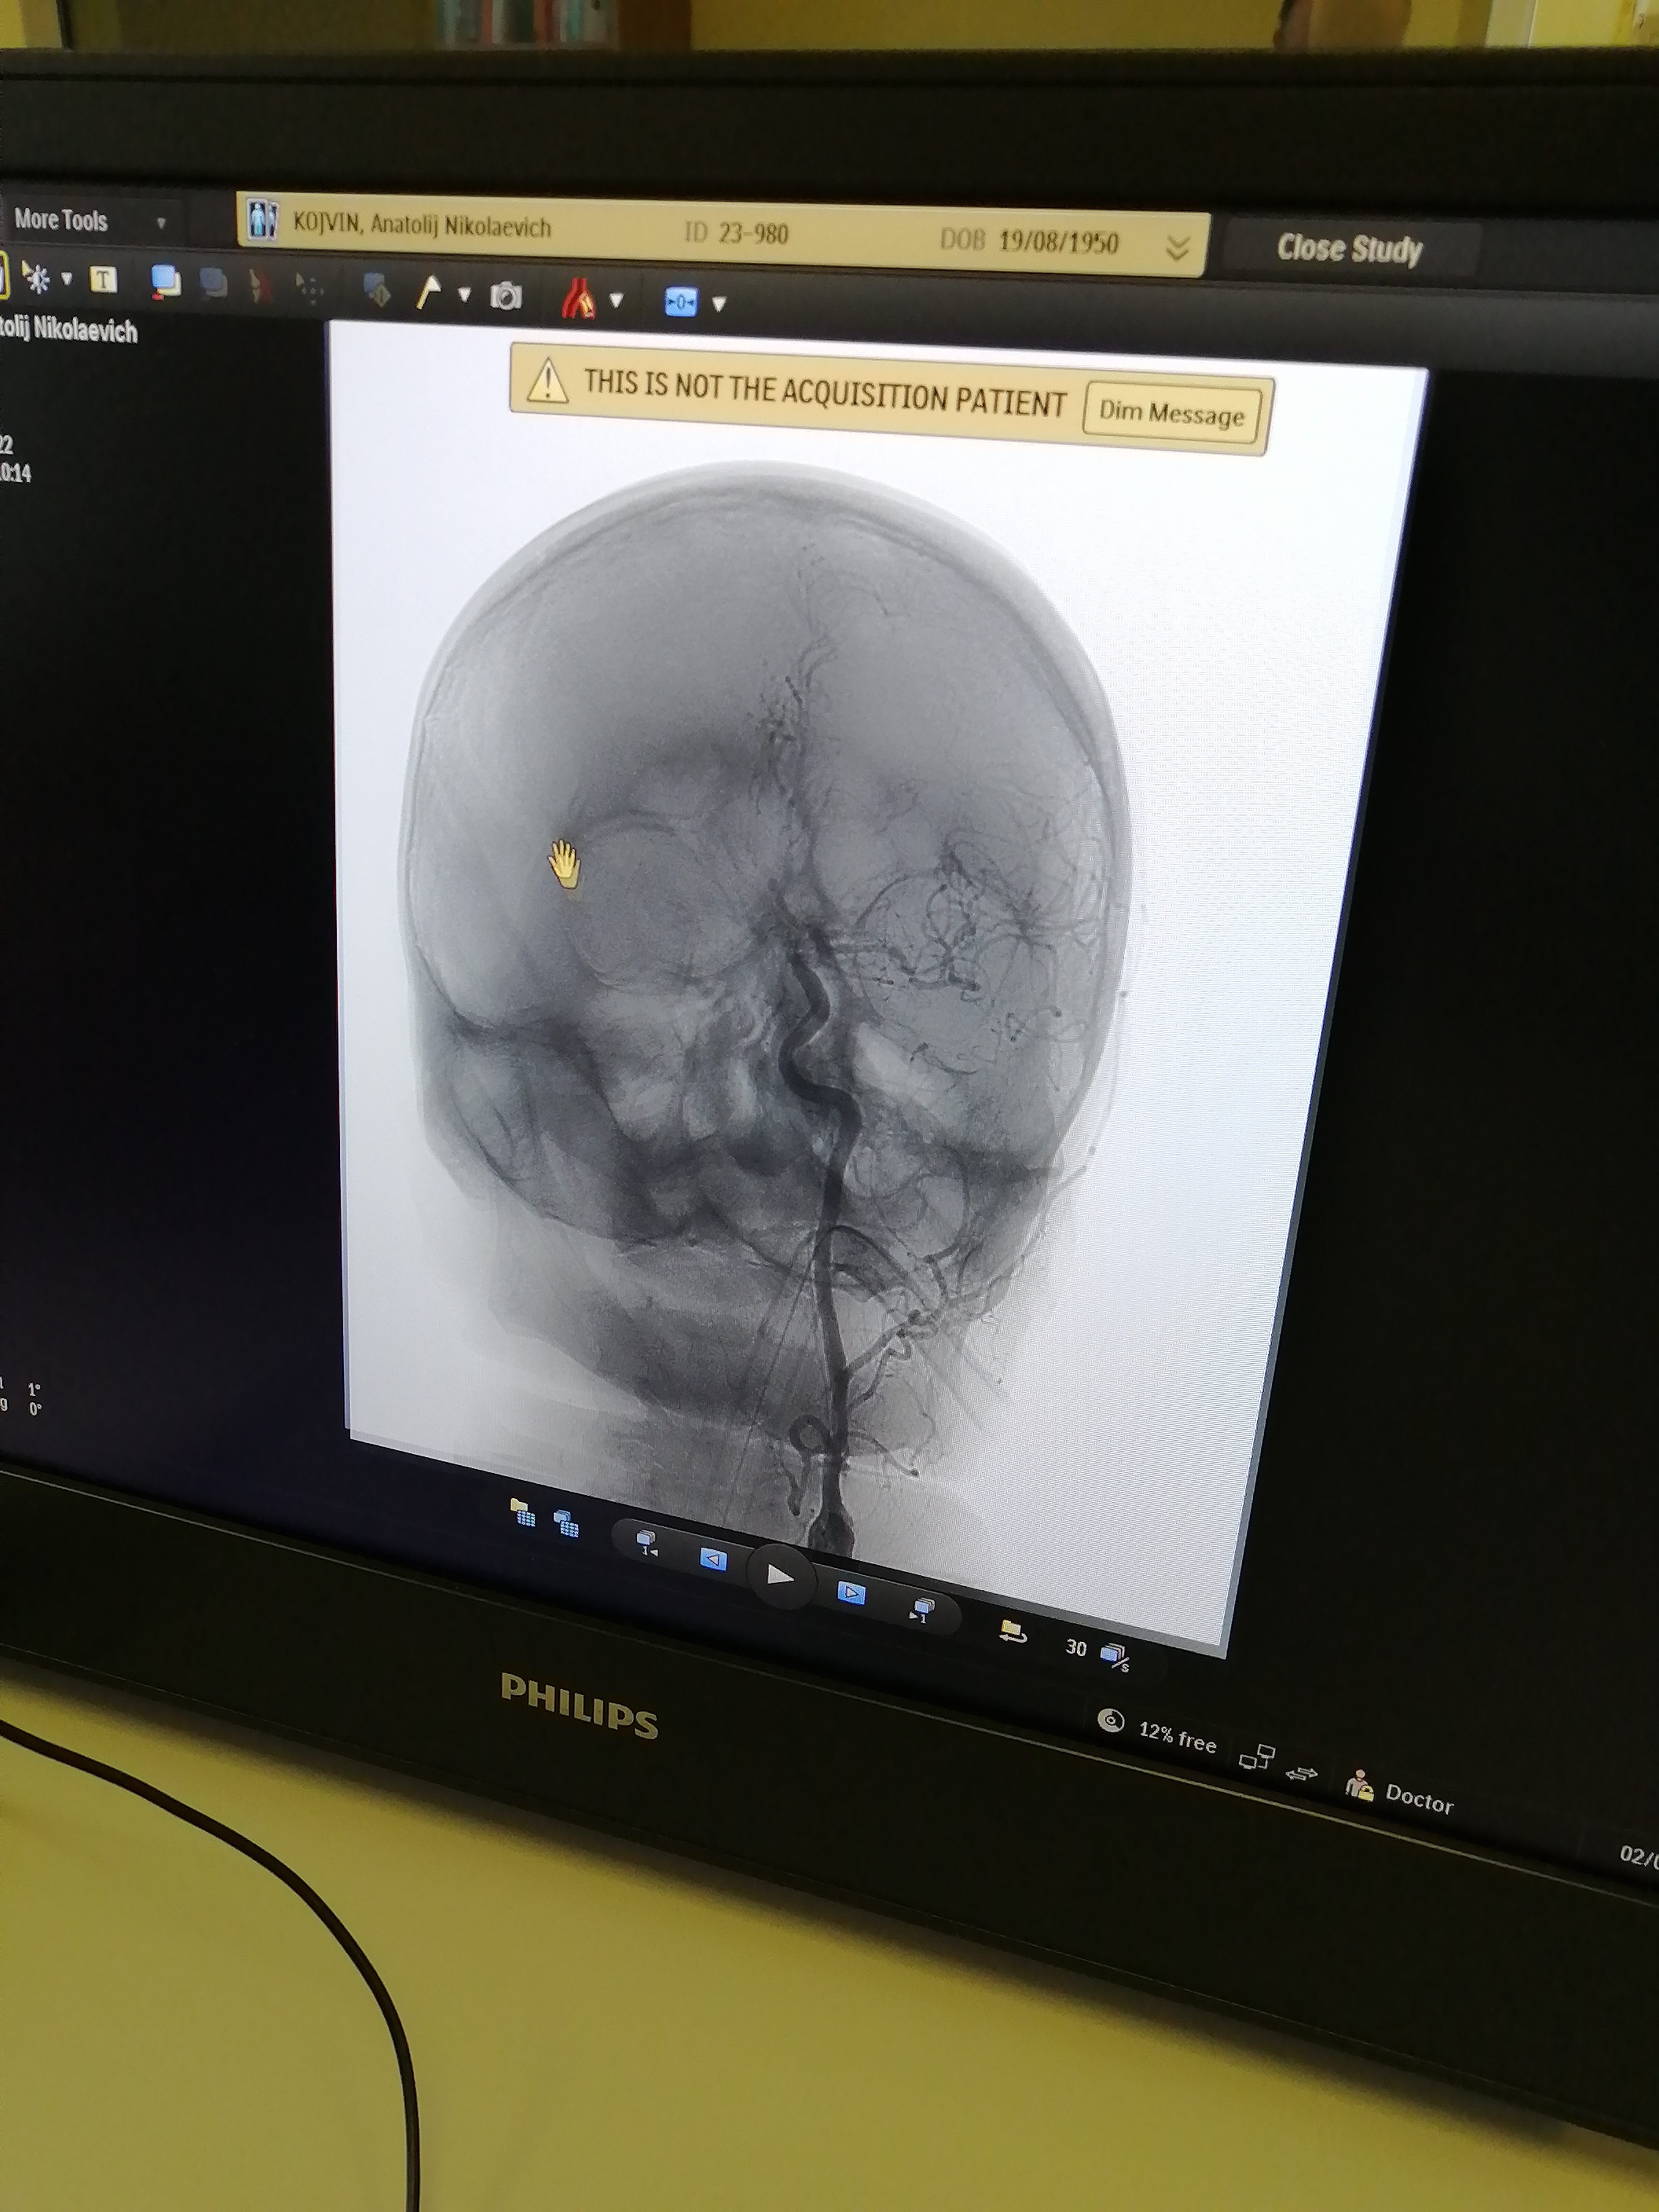

-К шейному и внутричерепному сосудам достаточно было одного доступа – через бедренную артерию. Сначала работали со стенозом - он затруднял доступ к аневризме, расположенной выше по кровотоку. Стентирование сонной артерии само по себе непростое вмешательство с использованием большого набора инструментов. Например, здесь необходимо устанавливать так называемые ловушки для тромбов, чтобы исключить их попадание в кровоток. Сложность в лечении аневризмы была связана как с её размерами – всего 3 миллиметра в диаметре, так и дистальным расположением – дальше «Виллизиева круга». При этом у неё оказалась достаточно широкая шейка, которая не смогла бы удержать микроспираль – специальную мягкую проволоку для заполнения мешка аневризмы и предотвращения дальнейшего поступления туда крови. Пришлось применить особую ассистирующую, то есть вспомогательную методику – с использованием специального микробаллона. В общей сложности операция заняла 2 часа 10 минут, - рассказывает рентгенохирург Екатерина Иванкова.